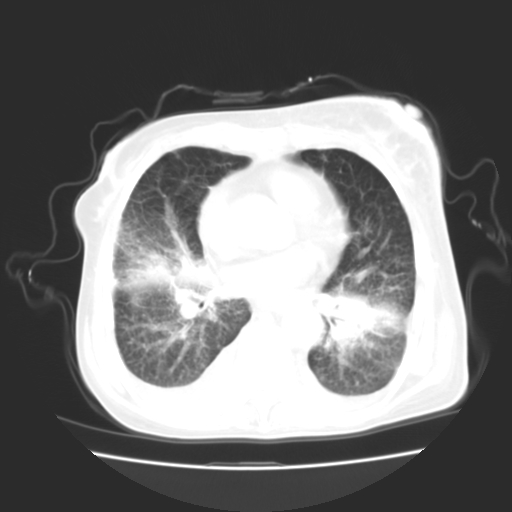

女70y乳腺ca(针吸活检)

多部位转移瘤的诊断可以肯定,我的疑问是:双肺对称高密度影及胸水是否为心衰肺水肿,病人体虚弱,不好意思图象传的乱![em9]

1)左侧乳腺癌并左侧腋窝及纵隔淋巴结转移,两肺淋巴道转移(癌性淋巴管炎),肝脏多发性转移。2)双侧胸腔积液。3)慢性胆囊炎。

3、双肺癌性淋巴管炎;

1)左侧乳腺癌并左侧腋窝及纵隔淋巴结转移,肝脏多发性转移。2)双侧胸腔积液伴双肺蝶翼样磨玻璃高密度影,双侧肺门血管影增粗(图像不全,肺门层面没纵隔窗),考虑心功能不全所致。3)慢性胆囊炎伴壁钙化。